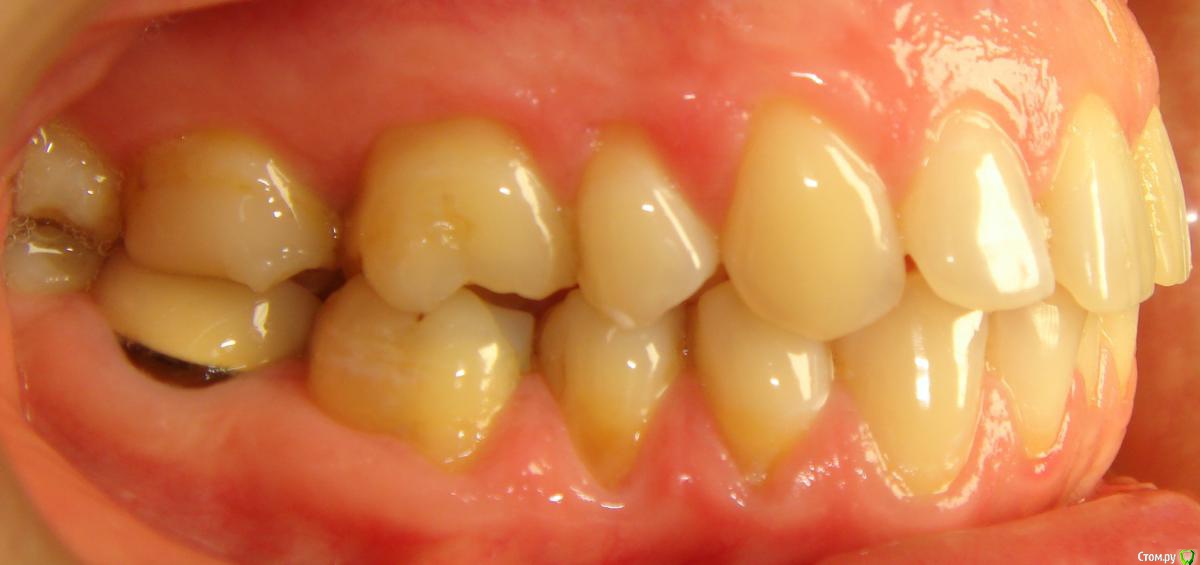

Opdihatop Опубликовано 16 апреля, 2017 Поделиться Опубликовано 16 апреля, 2017 Здравствуйте, коллеги! Что вы думаете по поводу этого случая? Объективно: вертикальный рост, первый костный класс. Незначительная протрузия резцов в/ч, нормальный наклон резцов н/ч. 15 зуб ретенирован. Значительное сужение в/ч, сужение н/ч.Вопросов 2: 1) Тянуть ли 15 зуб? 2) Планирую расширять при помощи SARPE, что делать с образовавшимся местом (которое и так сейчас уже есть)? Мне кажется такие большие реставрации будут некрасивыми. Ссылка на комментарий

Brigita Опубликовано 16 апреля, 2017 Поделиться Опубликовано 16 апреля, 2017 (изменено) Здравствуйте, коллеги! Что вы думаете по поводу этого случая? Объективно: вертикальный рост, первый костный класс. Незначительная протрузия резцов в/ч, нормальный наклон резцов н/ч. 15 зуб ретенирован. Значительное сужение в/ч, сужение н/ч.Вопросов 2: 1) Тянуть ли 15 зуб? 2) Планирую расширять при помощи SARPE, что делать с образовавшимся местом (которое и так сейчас уже есть)? Мне кажется такие большие реставрации будут некрасивыми.1) а куда его?2)Реставрации передних зубов имеется ввиду? Не такой большой промежуток, можно и реставрацию, если виниры не может позволить. расширение на SARPE - в таком возрасте без хирургии маловероятно, Вы же сами знаете, получите зубоальвеолярное небольшое расширение и наклон. Такой тонкий биотип, что там еще с кортикалкой будет. Мосты спаянные, вкладки. Чтобы узнать положение 5го надо КТ сделать, где у него корень - пойдет ли. Он видимо в небной костиА вообще - отдайте ее ортопедам. Она сама то что хочет? Изменено 16 апреля, 2017 пользователем Brigita Ссылка на комментарий

Brigita Опубликовано 16 апреля, 2017 Поделиться Опубликовано 16 апреля, 2017 Черные треугольники заполнить и рецессии убрать. я вот чего то не понимаю наверно.. где треугольники, которые она хочет убрать? я вижу диастему, трему 22-21, кариес 11-12, многочисленные рецессии, плохие ортопедические коронки, неправильно выполненные вкладки ( а может правильно? я не ортопед), скученность нижних зубов. А вообще вот интересно - в каком возрасте максимально возможно расширение на SARPE, у кого какой опыт? Ссылка на комментарий